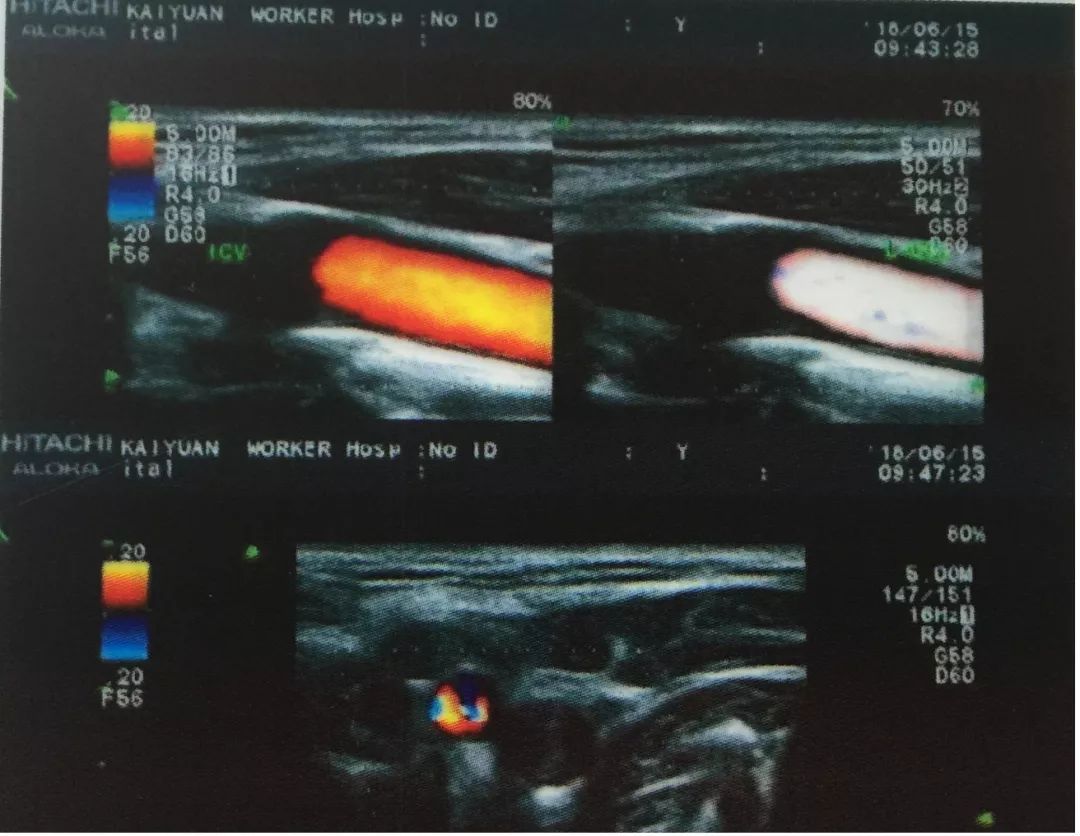

今年60岁的杨进聪,突然出现右侧肢体活动不灵,并伴有言语不清的症状。其从砚山县城迅速赶到开远工人医院就医,入院后,紫主任立即对他进行了颈部血管超声检查,发现其双侧颈总动脉粥样斑块形成(混合斑);右侧颈内动脉狭窄;左侧颈内动脉重度狭窄,甚至闭塞声像图;狭窄段收缩峰值明显增高,远端血流频谱呈“小慢波”。

图为左侧颈内动脉闭塞超声图谱,图片由功能科提供

杨进聪住院期间,紫主任对其进行了DSA全脑血管+主动脉弓造影检查,明确诊断为:1、左侧颈内动脉次全闭塞。2、右侧颈内动脉起始段中度狭窄。DSA与超声结论高度吻合。